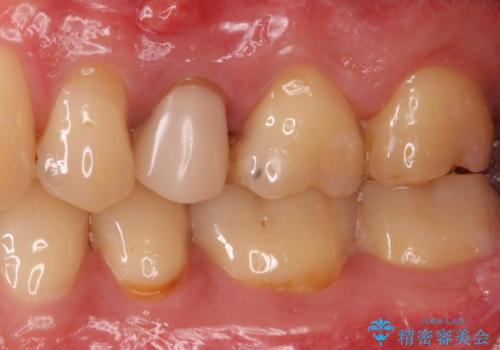

- 左上5:再根管治療(リトリートメント・小臼歯)/121,000円、土台(ファイバーコア)/22,000円、仮歯/11,000円、ジルコニアクラウン(スタンダード)/121,000円 合計275,000円(税込)費用は治療当時の料金となります

根管内の感染源を可能な限り除去し洗浄しました。

術後は腫れがなくなり特に症状も出ず、メンテナンスに移行しました。